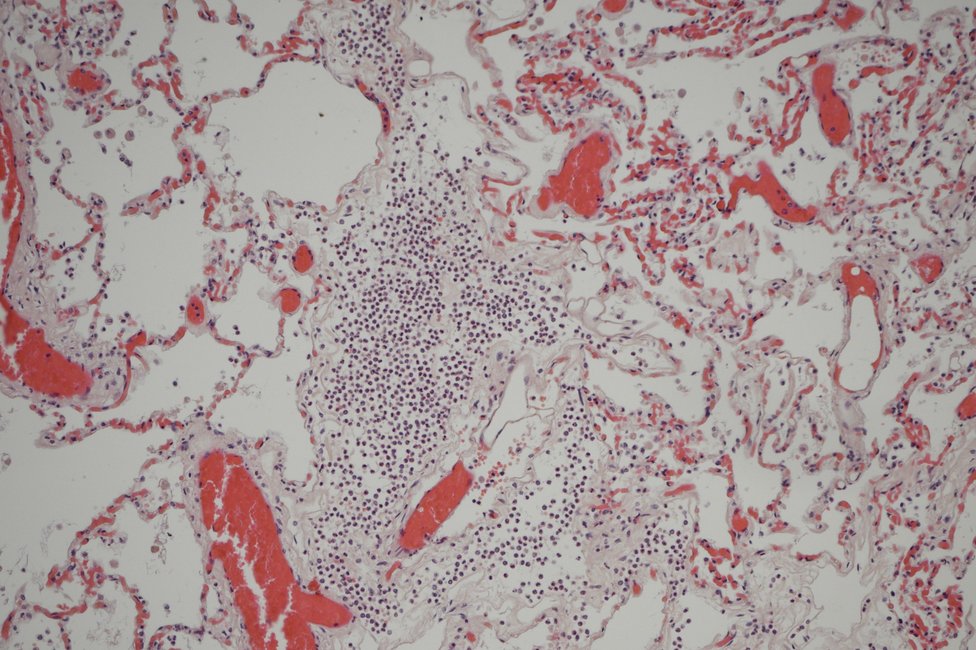

Forensic histology assumes an essential role in the context of forensic post-mortem examinations, since specific histochemical and immunohistochemical staining methods can be used to detect statements about the cause of death, e.g., early organ damage caused by oxygen deficiency, but also to determine the age of injuries and to perform vitality tests.